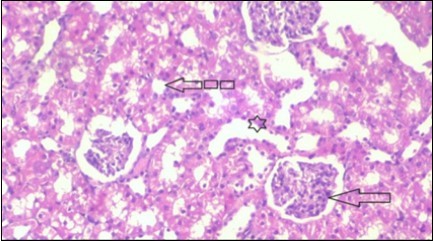

Kidney Histopathological Observations

Kidney sections of diabetic rats showed an increase in mesangial cell and matrix of glomeruli with increase in glycogen deposition and hyalinization of arterioles with thickened basement membranes of proximal and distal convoluted tubules. These changes will lead to progressive reduction in the filtration surface of the glomeruli 35. Histological examination of the kidney of the control rats showed normal structure of renal glomerular. The proximal and distal tubules were lined with normal epithelium (Figure 13). The diabetic rats showed tubular casts, inflammatory cellular infiltration and glomerular atrophy (Figure 14). Kidney of rats in groups (3 and 4) showed some glomeruli return to be normal (G). Focal tubules casts (T) in Fenugreek group and some normal tubules in the Glimepiride group with no inflammatory cellular infiltrate in both groups (Figure 15 and Figure 16). However, kidney of rats in group (5) showed normal glomerular (G), normal tubules (T) with no tubular casts (Figure 17).

Figure 13.photomicrogragh of kidney section of control rat showing normal rounded Bowman,s capsules with normal glomeruli (arrow) ,round proximal tubules (dash-arrow) and elongated distal tubules with high cuboidal cells (star) . (H&E) (40X)

Figure 14.Photomicrogragh of kidney section of diabetic rat showing a trophy of Bowman,s capsules and damage of glomeruli (arrow) and damage of distal and proximal tubules with congested blood vessels (star) . (H&E) (100Px).

Figure 15.Photomicrogragh of kidney section of treated rat with Fenugreek showing improvement of Bowman,s capsules with normal glomerular (arrow) and nearly return of distal tubules (dashed –arrow) and proximal tubules (star) (H&E) (40xX).

Figure 16.Photomicrogragh of kidney section of treated rat with Glimepiride showing improvement of Bowman,s capsules and partial improvement of glomerulir (arrow) and completely return of distal tubules and proximal tubules to the normal shape with wide urinary space. (H&E) (40X).

Figure 17.Photomicrogragh of kidney section of treated rat with both Fenugreek and Glimepiride showing improved cortical tissue with most of both Bowman,s capsules (arrow) and proximal tubules (dash-arrow) with nearly normal structure .Note distal tubules still suffering (star). (H&E) (40X).